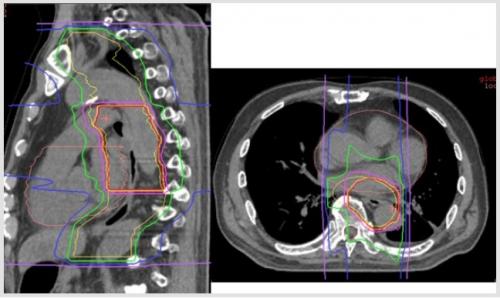

線量分布のご紹介

以下が当院で実際に治療された患者さんの線量分布です。12回照射では、1日1方向ずつ、前後2方向から照射します。